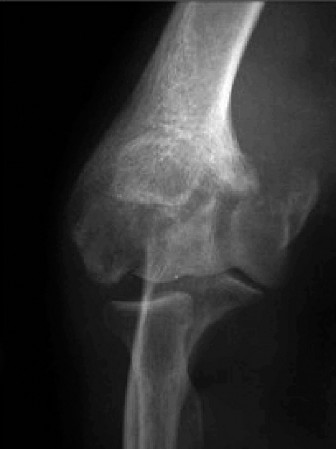

The correct answer is (C). Although pectoralis major muscle (PMM) injuries are

primarily diagnosed clinically, MRI is the imaging modality of choice to evaluate a PMM tendon injury. The extent and location of the injury can many times be assessed with MRI. The Tietjen’s classification system can be used for PMM injuries. Type I is a contusion or sprain. Type II is a partial tear. Type III injuries are complete tears and further classified by anatomic location: III-A (muscle origin), III-B (muscle belly), III-C (musculotendinous junction), III-D (tendinous insertion). Further subclassification were suggested including III-E (bony avulsion from the insertion) and II-F (muscle tendon substance rupture). Type II and Type III injuries have been reported at rates of 9% and 91%, respectively. Among complete tears, type III-D has been reported as the most common (65%). Ultrasound is a reasonable alternative to MRI, particularly if its use means avoiding delay of surgical repair. Ultrasound is much more user-dependent. CT will not allow adequate soft tissue evaluation. Further radiographic evaluation is incorrect because a radiograph of the injured shoulder has already been obtained. The radiographic findings are often normal, but the clinician should look for bony avulsions. The characteristic findings on radiographs are soft tissue swelling and absence of the PMM shadow.

After evaluating the MRI, the patient is diagnosed with a complete rupture of the pectoralis major tendon (Fig. 2–79). What is the recommended first step in management?

Figure 2–79